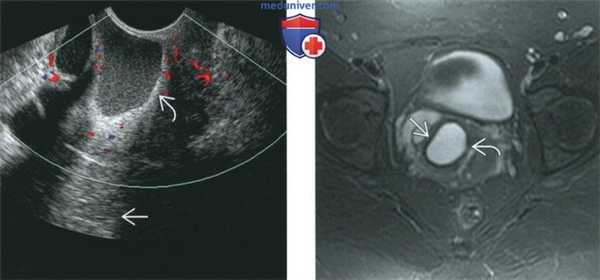

(Слева) При ТВУЗИ в продольной плоскости с применением ЦДК в стенке влагалища выявляется гипоэхогенное аваскулярное объемное образование. Наличие феномена акустического усиления задней стенки подтверждает кистозный характер объемного образования.

(Справа) При МРТ на Т2-ВИ в аксиальной плоскости у той же пациентки в переднебоковой стенке влагалища определяется гиперинтенсивная киста с четкими границами и гомогенной структурой. Визуализируется окаймляющий кисту бледный гипоинтенсивный ободок, который обусловлен отложением ге-мосидерина после ранее произошедшего кровоизлияния.